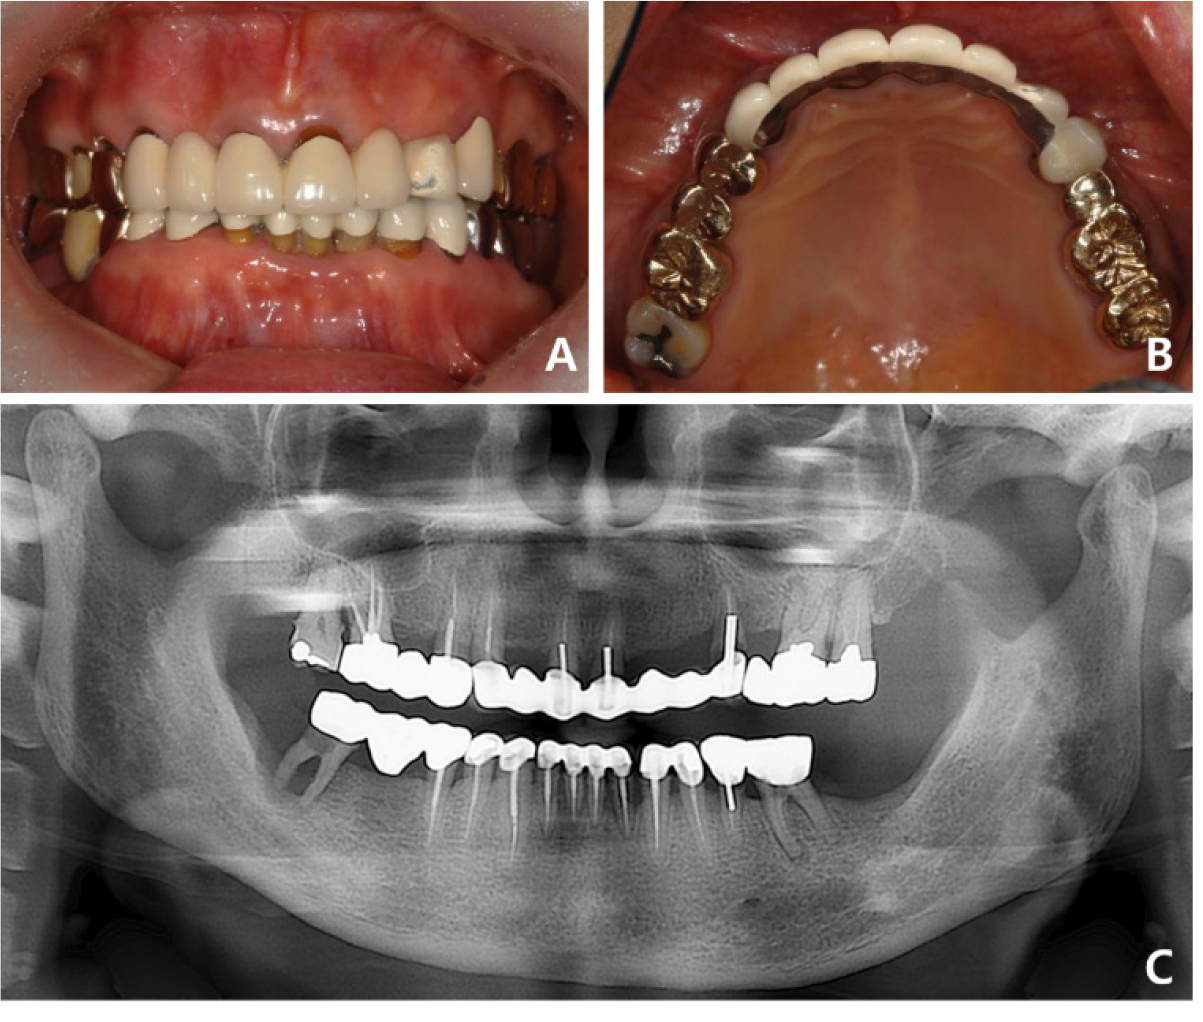

A 63-year-old woman who was on medication for hyperlipidemia visited the Department of Prosthodontics at Gangnam Severance Dental Hospital because she wanted to change old bridges due to porcelain fractures. Clinical and radiographic examinations revealed secondary dental caries in the maxillary left first premolar under an anterior 7-unit FPD (Fig. 5). Because it was necessary to extract a terminal abutment tooth, implant placement at sites #23 and #25 was planned for the rehabilitation of the left lateral incisor, canine, and premolars. A 4-unit implant-supported FPD with a #22 mesial cantilever was planned, and the patient agreed to the treatment plan of implant-supported FPD for improved aesthetics and function.

Fig. 5.

Case 2: Intraoral and radiographic views at the patient’s first visit. (A) A porcelain fracture is observed on the labial side of tooth #23 of the maxillary anterior ceramic prosthesis, (B) Seven-unit splinted maxillary anterior prosthesis from tooth #13 to tooth #24, (C) Panoramic radiograph suggests secondary caries in the abutment tooth #24.